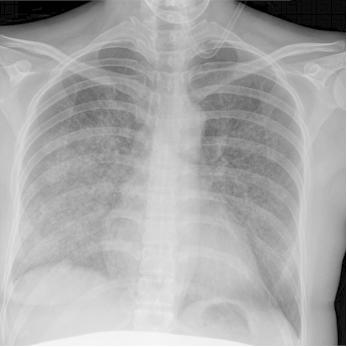

入院2天后,小美静养时突发咳嗽和呼吸困难,血压175/85mmHg,肺底可闻及粗湿啰音,文丘里面罩吸氧(FiO₂ 40%):动脉血气示低氧血症(PaO₂/FiO₂ 237 mmHg);血常规示贫血(血红蛋白浓度8.7g/dL)和血小板减少(126×109/L);NT-proBNP 4077pg/mL;胸部X线可见广泛模糊影(图2)。

图2.患者肺部X线可见广泛模糊影[2]怕什么来什么,科里怀疑患者先兆子痫合并溶血、肝酶升高、低血小板,即HELLP综合征(图3),考虑患者肺部的广泛模糊影是急性肺水肿,因此立刻给呋塞米治疗,但利尿后呼吸困难并没有改善。